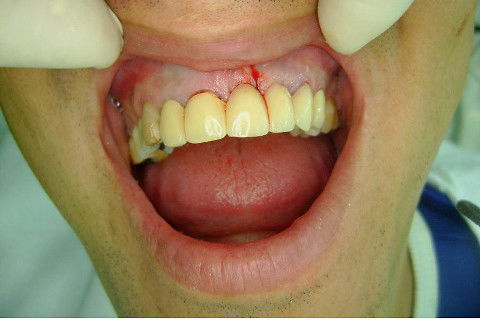

Paciente apareceu em meu consultório em dezembro/2013 para resolver problema de insatisfação com ponte fixa provisória anterior, realizada há 9 anos atrás (2004)...pretendia realizar somente a reabilitação em maxila/anterior, não contava com outros problemas com maior gravidade na sua boca, o máximo que citou foi a indicação para a exodontia do 16...

Cirurgia realizada hoje de manhã...No planejamento percebi medindo espessura do rebordo com especímetro que as medidas não estavam muito boas, ou o ideal, em torno de 4,5 a 5 mm ate´o terço médio do rebordo e melhorava no final, com 6 a 7 mm. Optei então por uma pequena expansão usando os expansores rosqueáveis. Aconteceu uma pequena fenestração na hora da fixação dos implantes, especialmente na região do 22 que fraturou o início da tábua óssea, mas não me preocupei porque não foi mais do que 2 mm de fratura em direção apical, o implante ficou infraósseo e com boa estabilidade (60 N no 21 e 40 N no 22). Esta fratura tb não deixou osso completamente solto, foi do tipo galho verde, deixei em posição e suturei normalmente. Só não fiz e nem estava planejado carga imediata mesmo, mais pelo motivo da oclusão inadequada do caso.